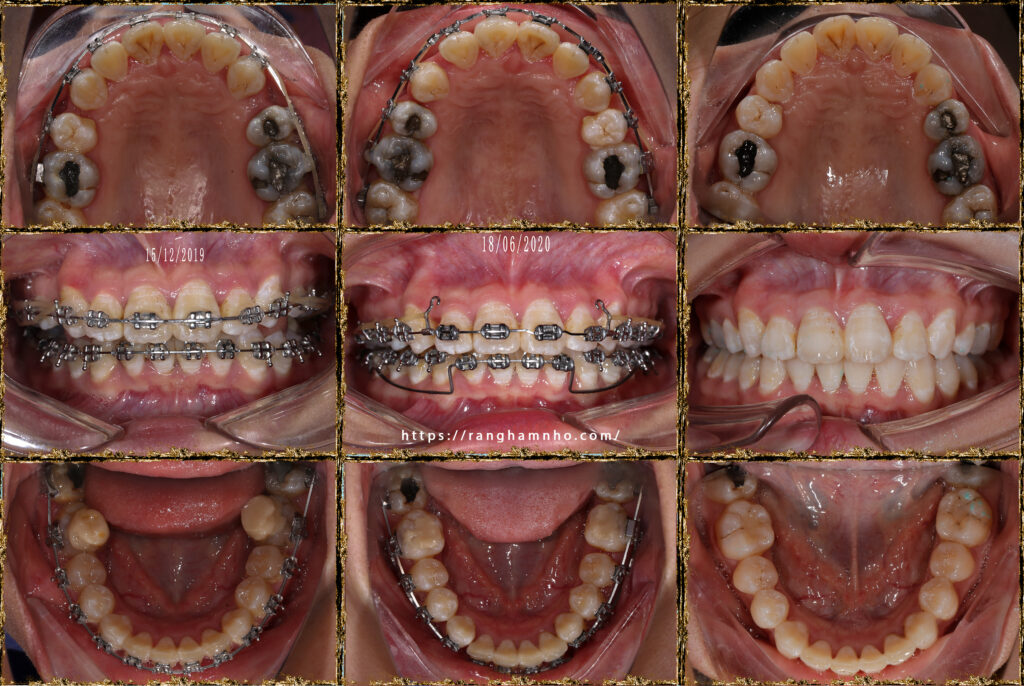

Hiệu ứng cuộn trong chỉnh nha (Bowing effect) là tình trạng các nhóm răng không dịch chuyển tịnh tiến theo mong muốn mà khi đó, các nhóm răng trước và nhóm răng sau bị “cuộn” lên gây hở khớp ở nhóm răng hàm nhỏ, nhiều trường hợp nặng gây hở cả khớp ở răng 6. Khi đó, các răng cửa và răng hàm đều trồi cao.

Có nhiều nguyên nhân gây hiệu ứng cuộn: lực kéo đóng khoảng quá mạnh, lực kéo đóng khoảng quá xa tâm cản, đường cong spee trước điều trị quá sâu, gắn sai mắc cài……..

Trường hợp này, bệnh nhân được chuyển lại cho Dr Răng Hàm Nhỏ trong tinh trạng đang có hiệu ứng uộn, và đang có hở khớp. Lập tức dừng ngay việc tác động lực để đóng khoảng, thay vào đó phải nhả toàn bộ lực kéo, đi lại dây cung niti mềm 1 tháng. Gắn mắc cài 2 ống cả 2 hàm, bẻ cung UA trên dây TMA 17×25 cả hai hàm, kích hoạt lực 75mg.

Kết quả: sau 2 tháng kết quả nhóm răng cửa đã được đánh lún khá tốt, mặt phẳng cắn được xử lí về bình thường. Tiếp tục quay lại đóng khoảng và kết thúc tháo mắc cài cho bệnh nhân.